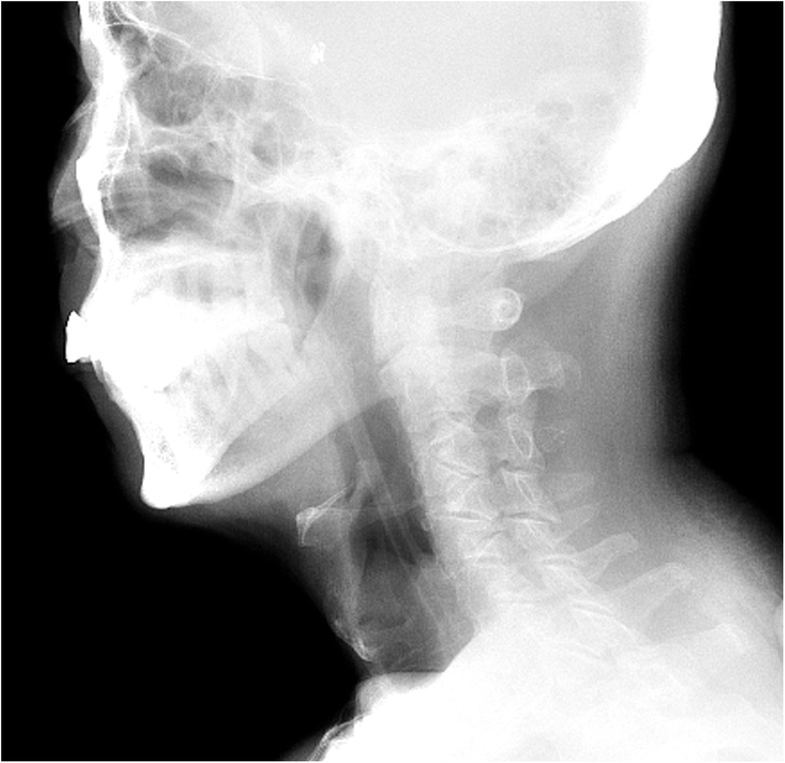

From therapyinsights.com

NG Tube Effect on Swallowing Physiology Adult and pediatric printable resources for speech and Ng Tube Long Term Effects this is why it is important to confirm the placement each time before a feed. using an ng tube for too long can also cause ulcers or infections in your sinuses, throat, esophagus, or stomach. how long can an ng tube stay in? the feeding tube is an external agent, therefore, its long dwelling time, without. Ng Tube Long Term Effects.